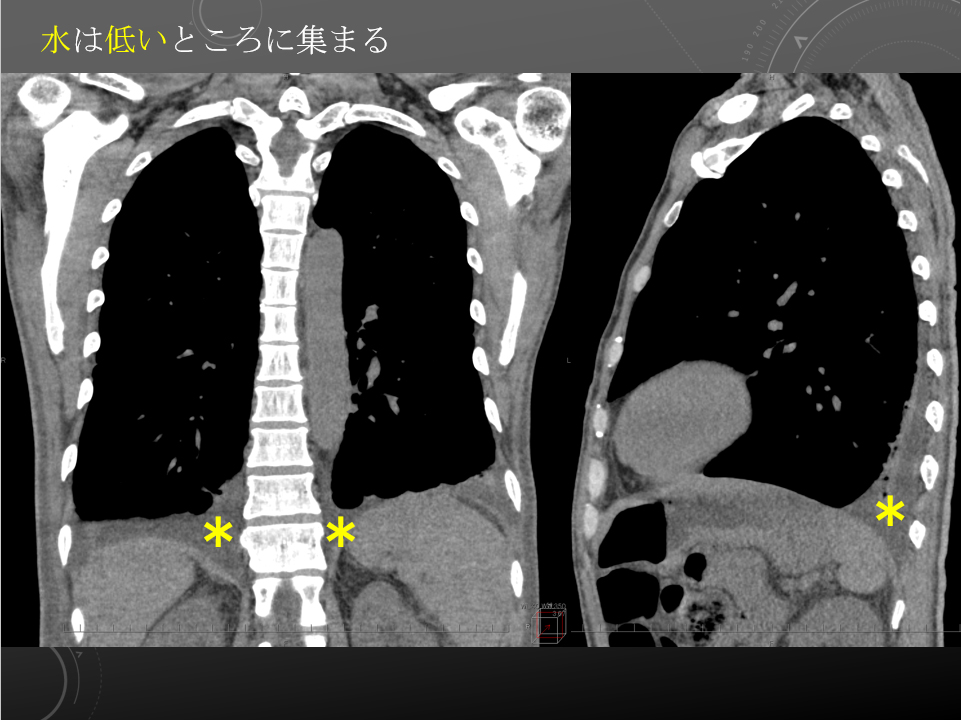

51M 脳梗塞

繰り返す嘔吐、腸閉塞などありますでしょうか。

前回のCT(2018/5/26)を参照しました。

両側胸水貯留を認めます。それに伴い、両肺下葉に受動無気肺が見られます。

その他、両肺に活動性病変は指摘できません。

胸部に有意な腹部リンパ節腫大は指摘できません。

心膜洞の液体貯留と思われる気管右前方の低吸収域に著変ありません。

積極的に腸閉塞を疑うような腸管拡張は見られず、嘔吐の原因も同定できません。

膀胱壁の肥厚や軽度な水腎症・水尿管が見られ、慢性膀胱炎に伴う変化の可能性があります。水腎症・水尿管は前回より改善傾向です。

その他、腹腔内臓器に特記すべき異常は指摘できません。

腹部に有意なリンパ節腫大は見られません。

腹水貯留は見られません。

積極的に腸閉塞を疑うような腸管拡張は見られず、嘔吐の原因も同定できません。

51M 脳梗塞

繰り返す嘔吐、腸閉塞などありますでしょうか

前回のCT(2018/5/26)を参照しました。

両側胸水貯留を認めます。それに伴い、両肺下葉に受動無気肺が見られます。

その他、両肺に活動性病変は指摘できません。

胸部に有意な腹部リンパ節腫大は指摘できません。

心膜洞の液体貯留と思われる気管右前方の低吸収域に著変ありません。

積極的に腸閉塞を疑うような腸管拡張は見られず、嘔吐の原因も同定できません。

膀胱壁の肥厚や軽度な水腎症・水尿管が見られ、慢性膀胱炎に伴う変化の可能性があります。水腎症・水尿管は前回より改善傾向です。

その他、腹腔内臓器に特記すべき異常は指摘できません。

腹部に有意なリンパ節腫大は見られません。

腹水貯留は見られません。

積極的に腸閉塞を疑うような腸管拡張は見られず、嘔吐の原因も同定できません。